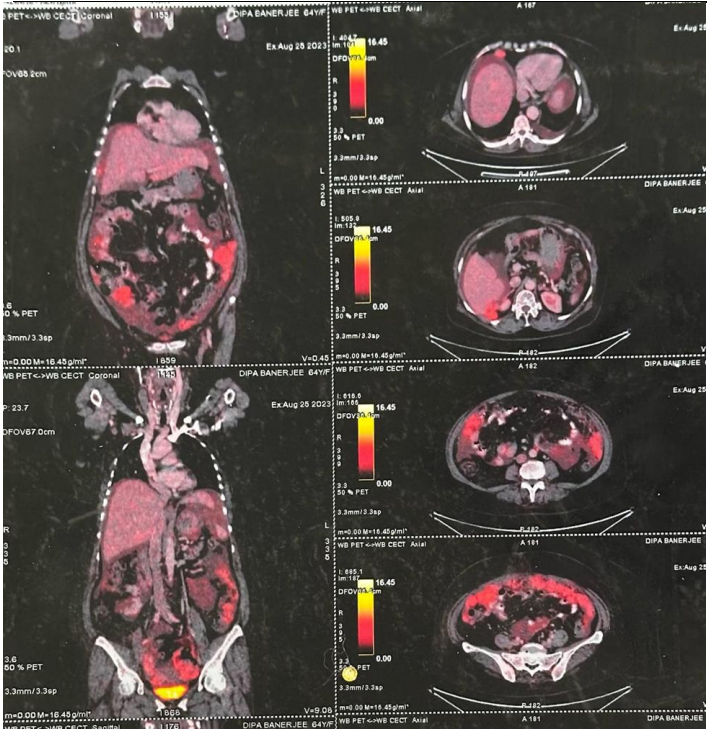

Fig 5

Second-line Therapy: FOLFIRINOX was initiated following disease progression, achieving significant interim response in PET CT scan [Fig.4]. Chemotherapy was continued with a plan to reassess for surgical intervention.

Figure 5